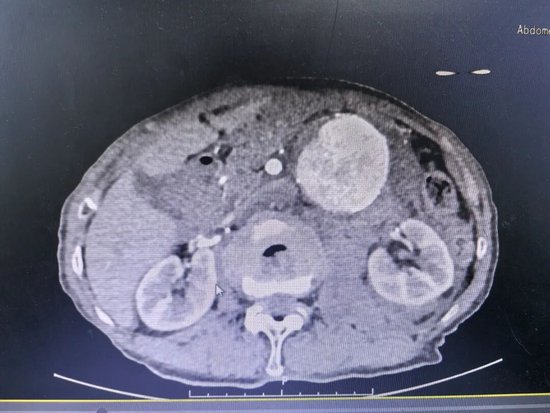

腹主动脉瘤,被称为“体内的不定时炸弹”,一旦破裂,死亡率极高。对于89岁的老人来说,这颗“炸弹”不幸被引爆。10月10日,患者因突发剧烈腹痛被紧急送入庆云县人民医院,经检查,确诊为腹主动脉瘤破裂出血,情况万分危急。

经过专家团队的全面评估和审慎决策,认为唯有行腹主动脉瘤腔内修复术(EVAR),才有一线生机。这是一种微创介入手术,仅需在双侧大腿根部切开约2厘米的小切口,通过股动脉将覆膜支架系统精准输送到动脉瘤部位,像搭桥一样在血管内建立起一道坚固的“屏障”,隔绝破裂的瘤腔,从而达到止血和治愈的目的。

造影显示,支架定位完美,动脉瘤被完全隔绝,活动性出血瞬间停止,手术取得了决定性成功!